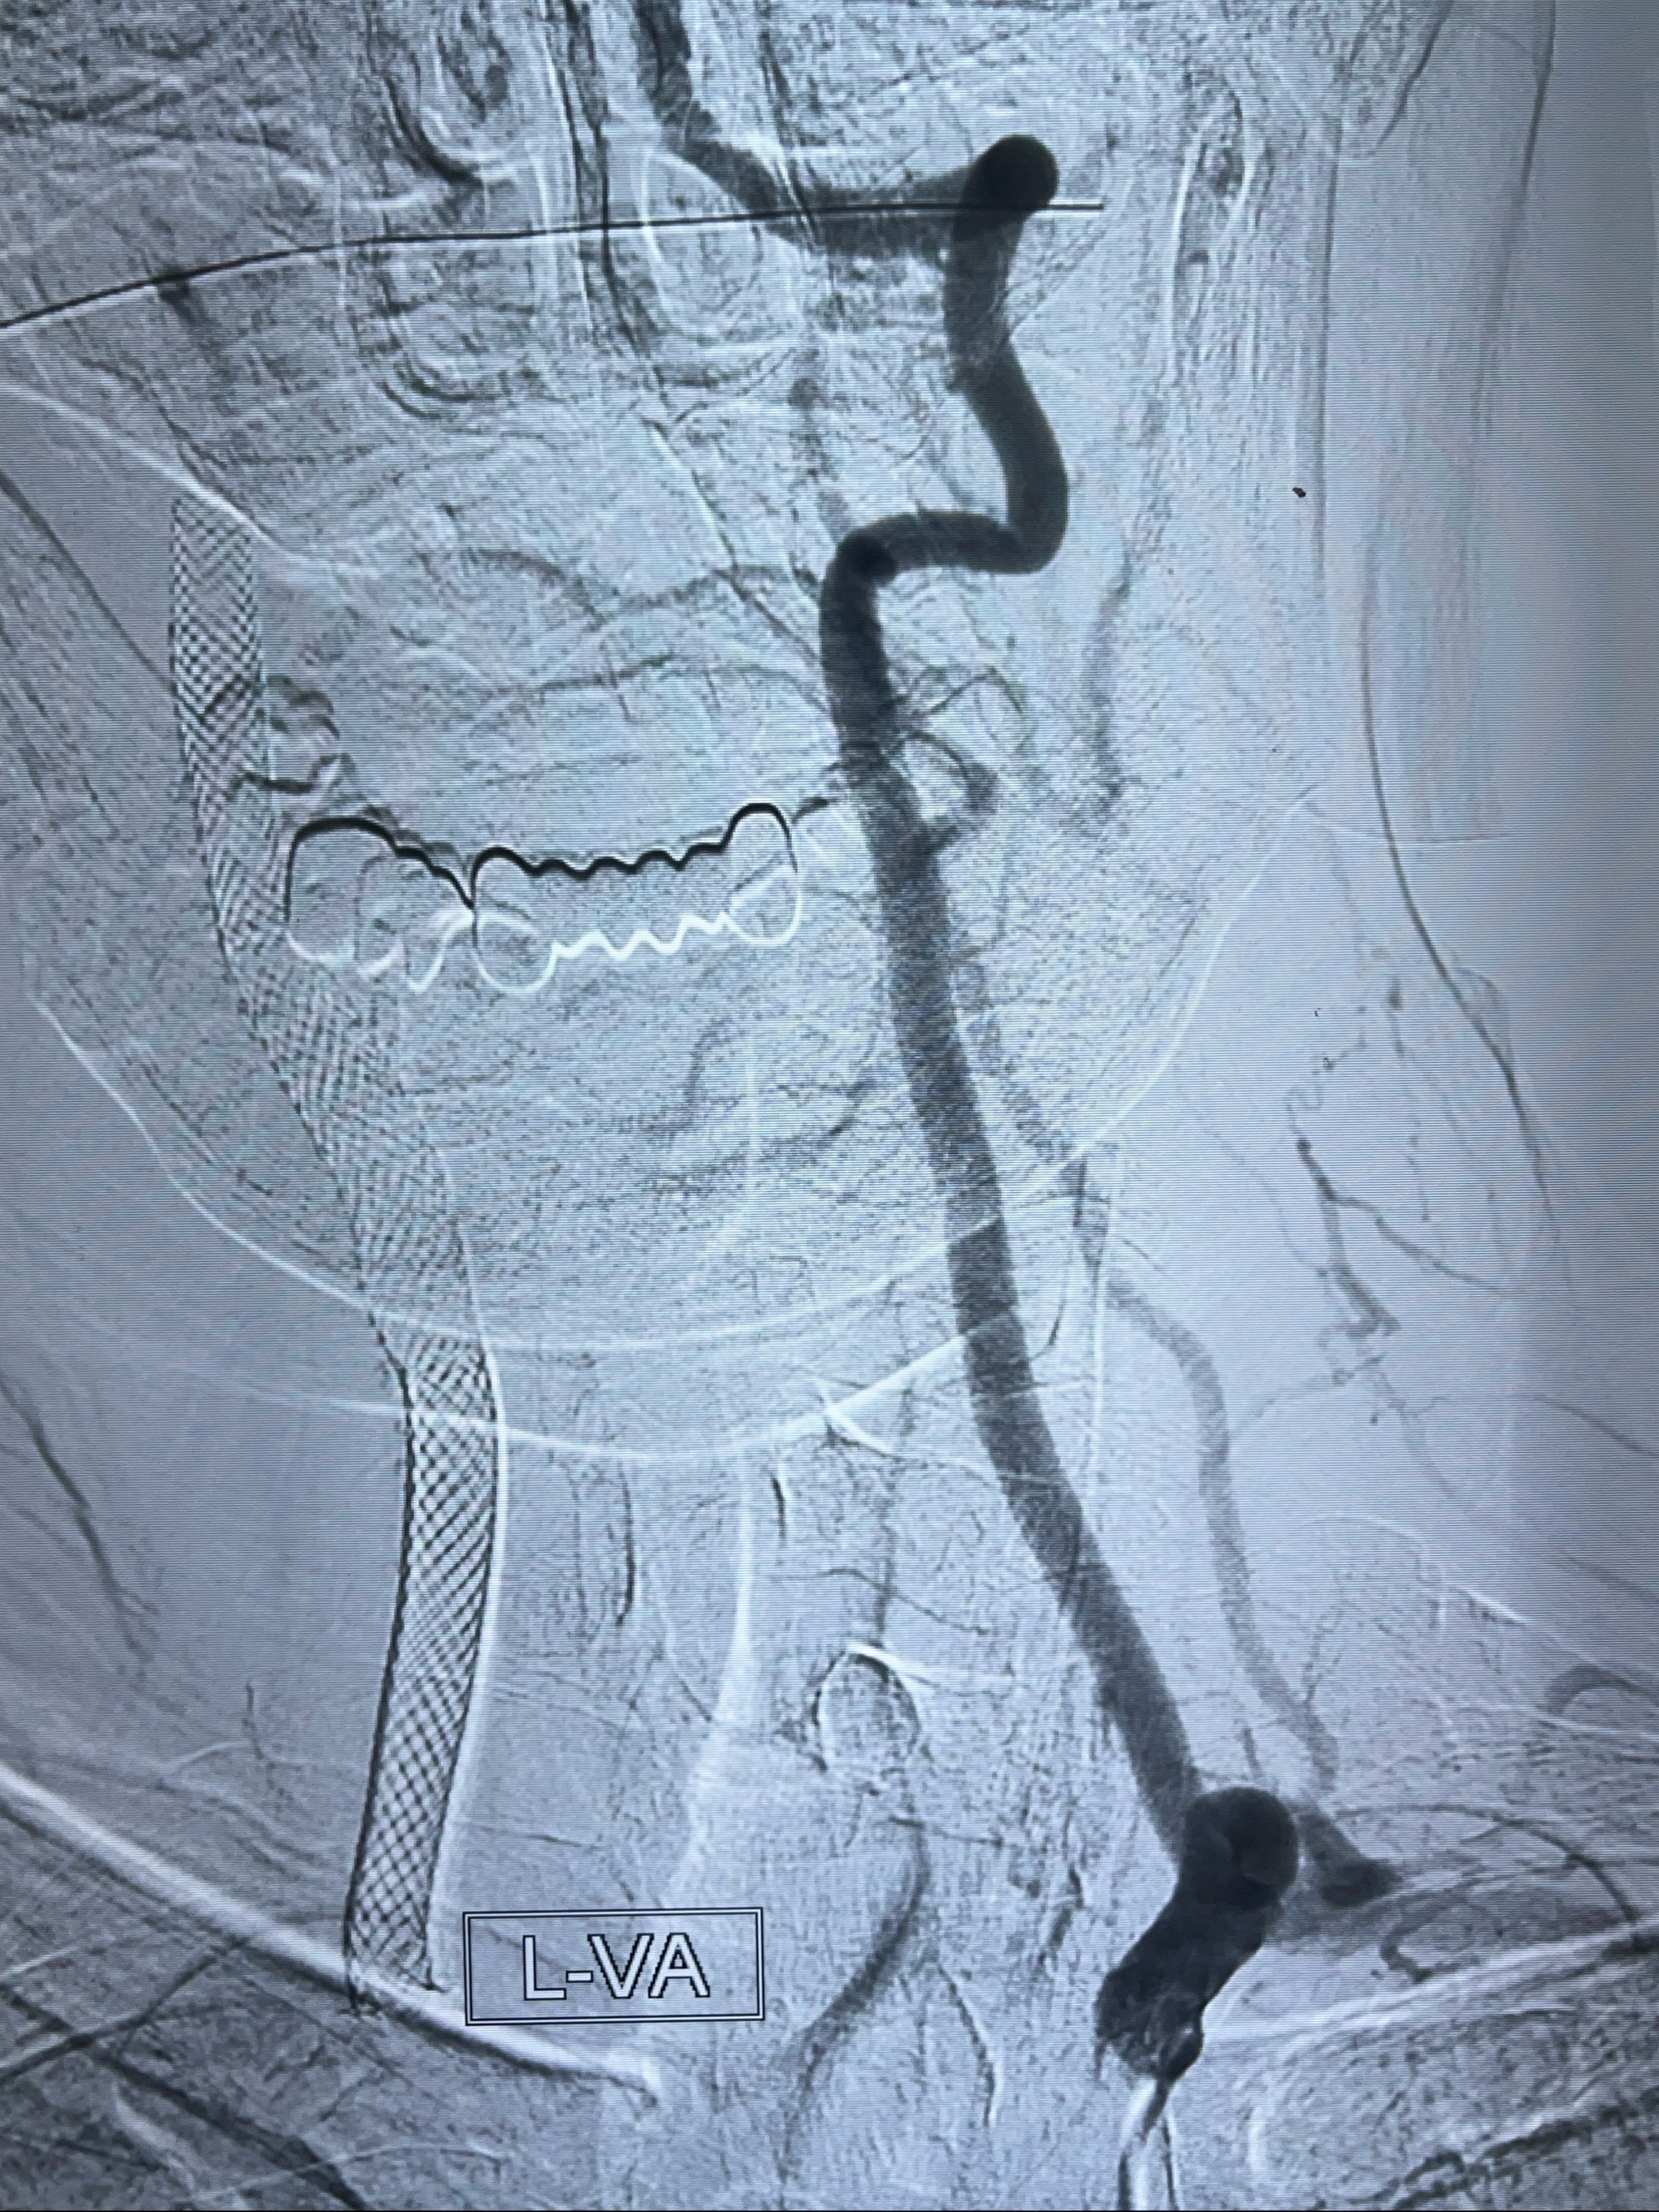

2023-07-10DSA:右侧颈内动脉岩骨段夹层伴中偏重度狭窄改变,左侧颈总动脉闭塞、右侧颈外动脉由右侧肋颈干甲颈干吻合代偿

箭头所示为颈内动脉岩骨段重度狭窄,结合MRI,考虑为肿瘤侵犯右侧颈内动脉

箭头以近至支架段管腔不规则狭窄

右侧椎动脉可见吻合代偿右侧颈外动脉

左侧颈总动脉起始段至分叉部闭塞,起始部呈现子弹头样改变

左侧椎动脉可见代偿显示左侧前循环